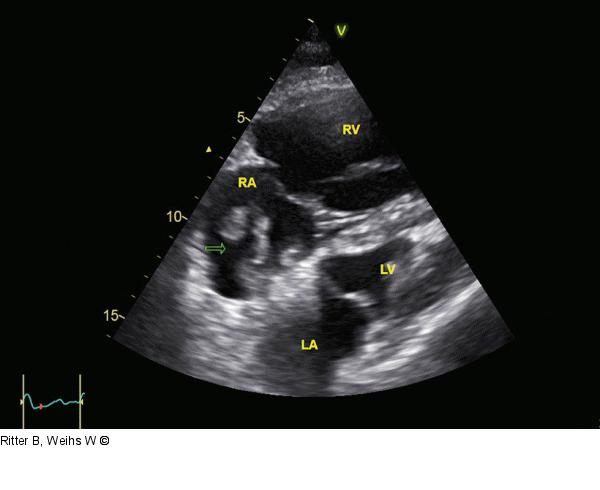

Abbildung 1: Vierkammerblick Initialer subkostaler Vierkammerblick. Massive Dilatation und Hypokontraktilität des rechten Ventrikels. Mobiler Thrombus (Pfeil) im rechten Vorhof. RA: rechter Vorhof; RV: rechter Ventrikel; LV: linker Ventrikel; LA: linker Vorhof |

Initialer subkostaler Vierkammerblick. Massive Dilatation und Hypokontraktilität des rechten Ventrikels. Mobiler Thrombus (Pfeil) im rechten Vorhof. RA: rechter Vorhof; RV: rechter Ventrikel; LV: linker Ventrikel; LA: linker Vorhof |